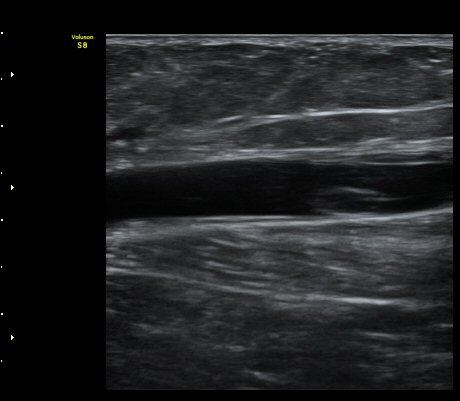

¹«¸ µÚ ¿À±Ý Á¾´Ü¸é°Ë»ç¿¡¼ ³»Ãøºñº¹±Ù°ú ¹Ý¸·¾ç±Ù »çÀÌ¿¡ Àú¿¡ÄÚ ¼ö¾×Àú·ù°¡ °üÂûµÈ´Ù(»çÁø 1).